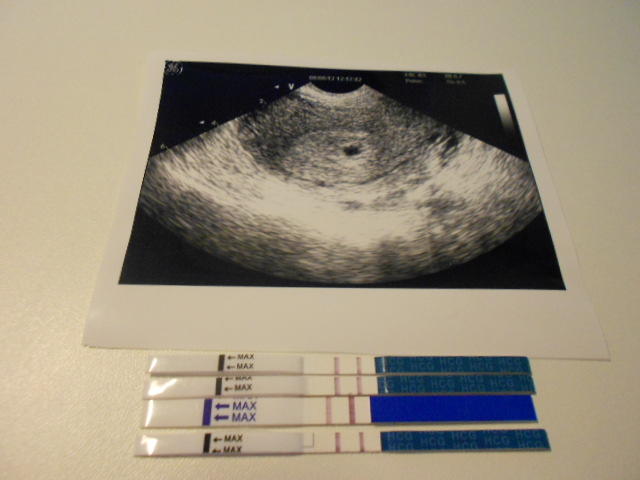

Фото Второй Беременности

Фото Второй Беременности 117 фотографий